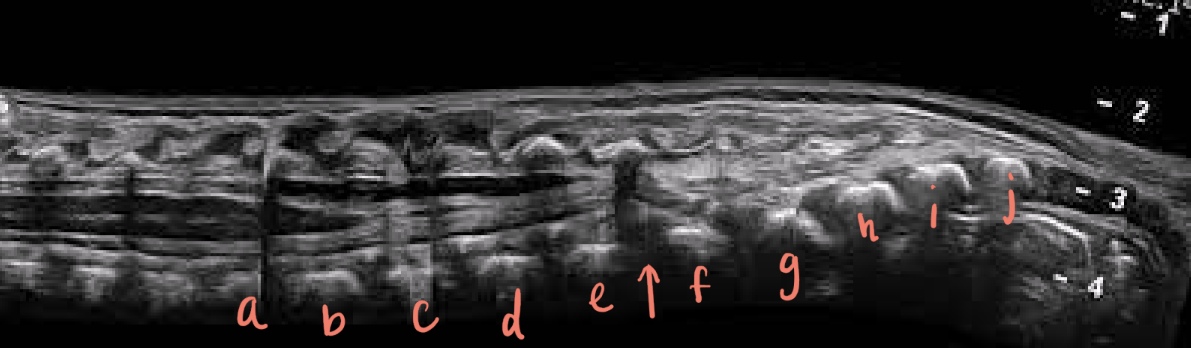

a

L1

b

L2

c

L3

d

L4

e

L5

f

S1

g

S2

h

S3

i

S4

J

S5

arrow

filum terminale

red arrow